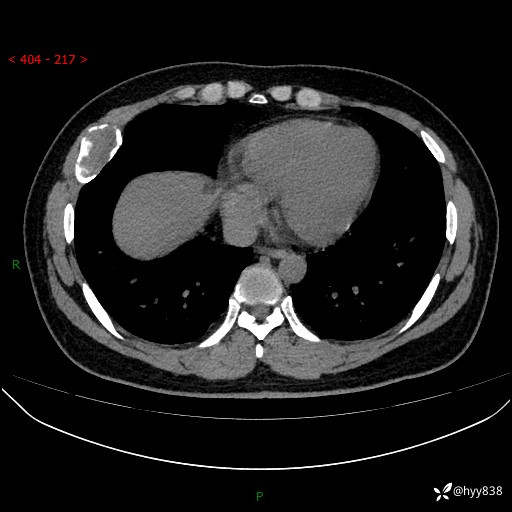

胸部CT平扫